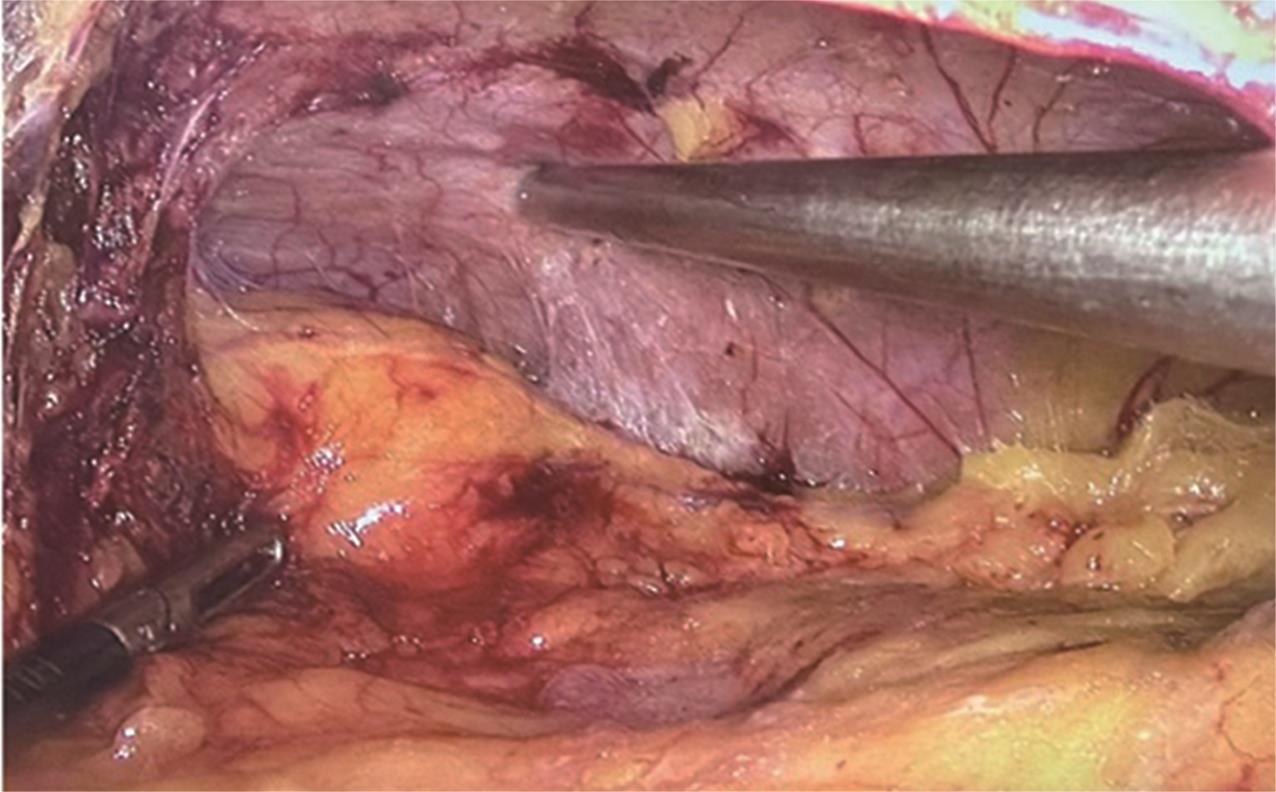

• 转移性上尿路上皮癌在维迪西妥单抗联合替雷利珠单抗新辅助治疗后行根治性肾盂癌切除术1例报道

2023, 48(8):1005-1008. DOI: 10.13406/j.cnki.cyxb.003299

摘要 (52) HTML (36) PDF 2.16 M (1929) 评论 (0) 收藏

摘要: